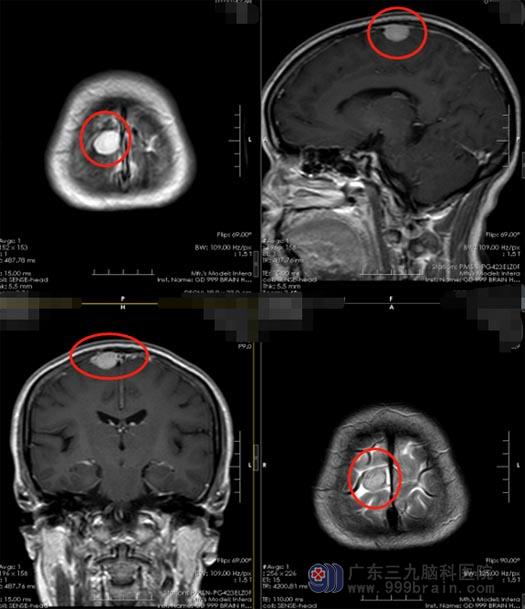

来到广东三九脑科医院,刘阿姨的颅脑影像检查提示“右侧顶部矢状窦旁小脑膜瘤”。知道了检查结果,刘阿姨和女儿都如临大敌,大脑是人的精神、语言、感情和行为的指挥中枢,这里面发现了肿瘤简直比癌症还可怕。

矢状窦旁脑膜瘤是起源于矢状窦附近的脑膜瘤,此部位的脑膜瘤手术难度相对大一些。由于脑膜瘤可能和矢状窦形成粘连,甚至侵犯矢状窦侧壁,手术中有可能会发生矢状窦破裂引起大出血,危及生命。并且肿瘤与矢状窦壁形成粘连包裹,手术中可能难以对肿瘤进行全切除,手术后肿瘤会复发,需要再次手术,或者行放射治疗来延缓肿瘤的复发速度。

▲手术前